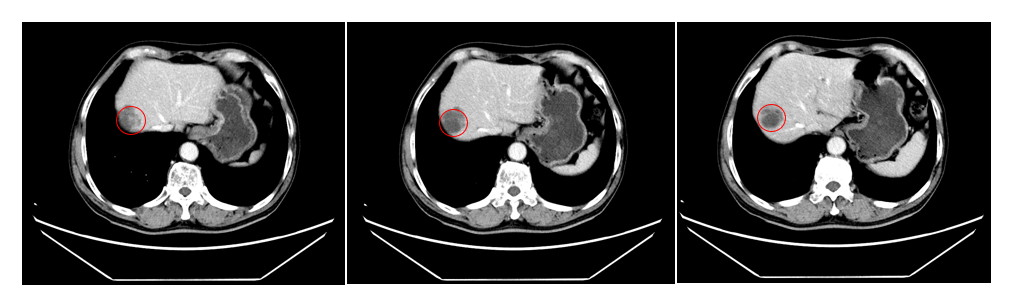

历经规范的SBRT立体定向放疗后,刘某复查CT结果传来捷报:与放疗前相比,肝内转移肿瘤病灶出现明显缩小,治疗效果确切,病情得到有效控制!

(▲放疗前CT图像)